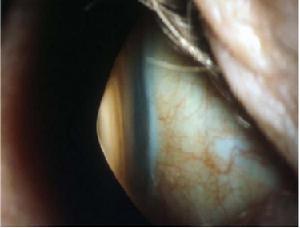

圓錐角膜(Keratoconus或縮寫為KC)是以角膜中央變薄向前突出,呈圓錐形為特徵的一種眼病。它常造成高度不規則近視散光和不同程度的視力損害,不伴有炎症。本病多發生於20歲左右的青年,通常為雙眼先後發病,原因不明。有人認為可能是遺傳性發育異常,也有人報告本病與內分泌紊亂和變態反應性疾病有關。